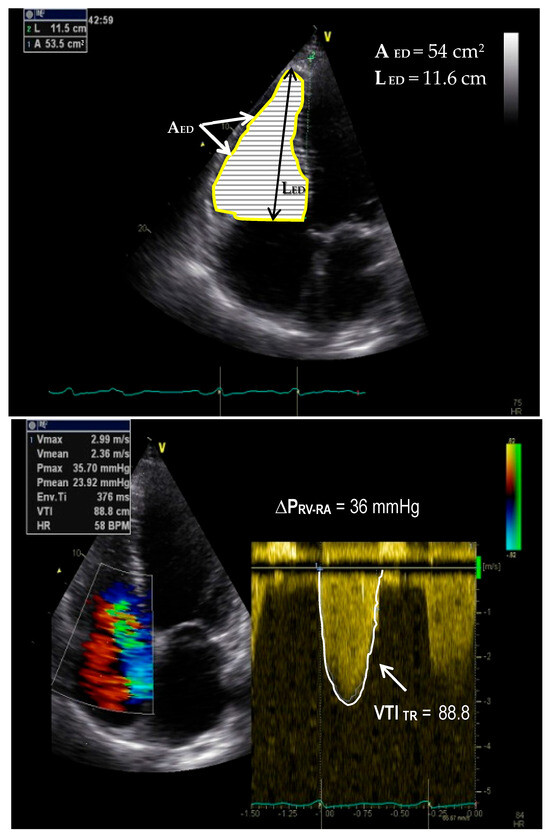

Assessment of Right Ventricular Adaptability to Pressure Overloading for Critical Therapeutic Decision-Making Processes

Right ventricular pressure overloading [RVPO] with secondary maladaptive RV remodeling and progressive myocardial dysfunction in patients with pulmonary hypertension associated with left-sided heart diseases [PH-LHDs] and in those with pulmonary arterial hypertension [PAH] still remains one of the most complex challenges in cardio-pulmonary [...] Read more.

Right ventricular pressure overloading [RVPO] with secondary maladaptive RV remodeling and progressive myocardial dysfunction in patients with pulmonary hypertension associated with left-sided heart diseases [PH-LHDs] and in those with pulmonary arterial hypertension [PAH] still remains one of the most complex challenges in cardio-pulmonary medicine. Despite the advances in the optimization of diagnostic tools and the expansion of treatment options, there is still a great need for further research to gain a better understanding of the major pathophysiological mechanisms involved in both the RV responses to PO and to find new possibilities to stop the progression of the alterations inside the pulmonary arterial circulation [PAC]. This article summarizes current knowledge about the particularities of the RV structural and functional responses to abnormal PO and also provides an overview of the benefits and limitations of the currently available tools for clinical evaluations of the RV adaptability to high afterload. A major focus of this review relates to the possibilities for obtaining evidence about the existence of a still remaining adaptability to a normal afterload in an over-burdened RV, in case of abolition of the pathological PO and, in this regard, to also evaluate the clinical usefulness of the RV adaptability estimation for certain critical therapeutic decisions. Among the most important conclusions of this updated overview are: 1. Whereas single parameters are insufficiently reliable for the evaluation of RV dysfunction and for predictions of its prognostic relevance across the whole spectrum of RVPO, properly selected and integrated multiparametric approaches had meanwhile unequivocally proved that they can usually become sufficiently reliable. 2. Multiparametric approaches can substantially improve the prediction of a preserved RV responsiveness to the abolition of its steady PO by reversal of RV maladaptive remodeling and by the normalization of RV pump function. Such a prediction, which can be decisive for therapeutic decision-making especially in candidates for ventricular assist device [LVAD] implantation or thoracic organ transplantation, can have a crucial impact on patient survival. 3. The complex and temporally highly variable interactions between certain structural and functional changes in both the PAC and in the hemodynamic overloaded right-sided heart, as well as between the two ventricles, can often hamper the interpretation of certain changes in the measured parameters and even relevantly alter their reliability. Additionally, the progressive aggravation of a secondary tricuspid regurgitation [TR] has a particularly high negative (often also misleading) impact on the diagnostic and prognostic relevance of RVPO evaluations. Full article